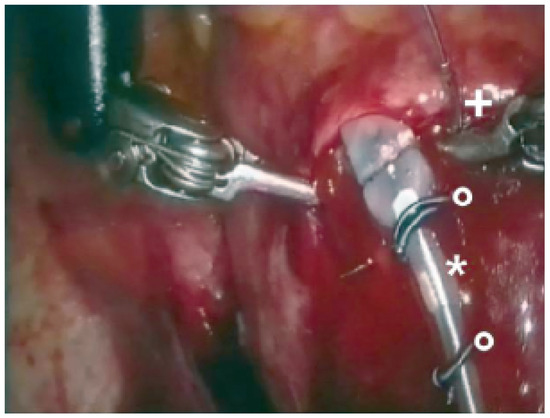

Biventricular pacing is an accepted therapy in patients suffering from terminal heart failure. Main obstacle however is the positioning of the left ventricular electrode via coronary sinus as well as its reliable fixation. This article describes in a...